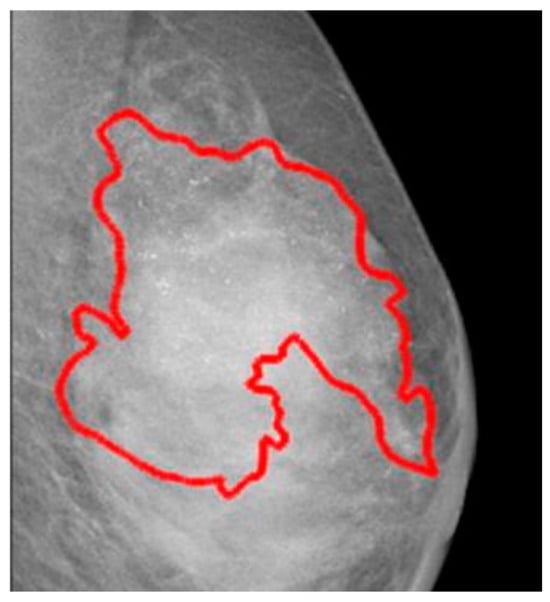

4.2.3. CSAW-CC

The CSAW-CC database offers various subsets suitable for cancer classification, detection, or segmentation in mammograms. However, not all samples feature detailed annotations with exact region of interest (ROI) contours, as presented in Figure 3. The pixel-level annotations encompass tumors identified at diagnosis, those noted during prior screenings, and areas where no tumors were present during earlier evaluations. These annotations provide measurements of tumor area (in square pixels) and the length of the major axis (in pixels) for both diagnosis and prior screenings. Tumors are categorized as invasive, in situ, or a combination of both. A limitation of the CSAW-CC database is the lack of specific BI-RADS scores. Similarly to the OMI-DB database, CSAW-CC’s primary advantage is its regular screenings, which might help to track tumor progression by using past annotations that show where tumors were located. Additionally, the database emphasizes real-world variability in age [19].